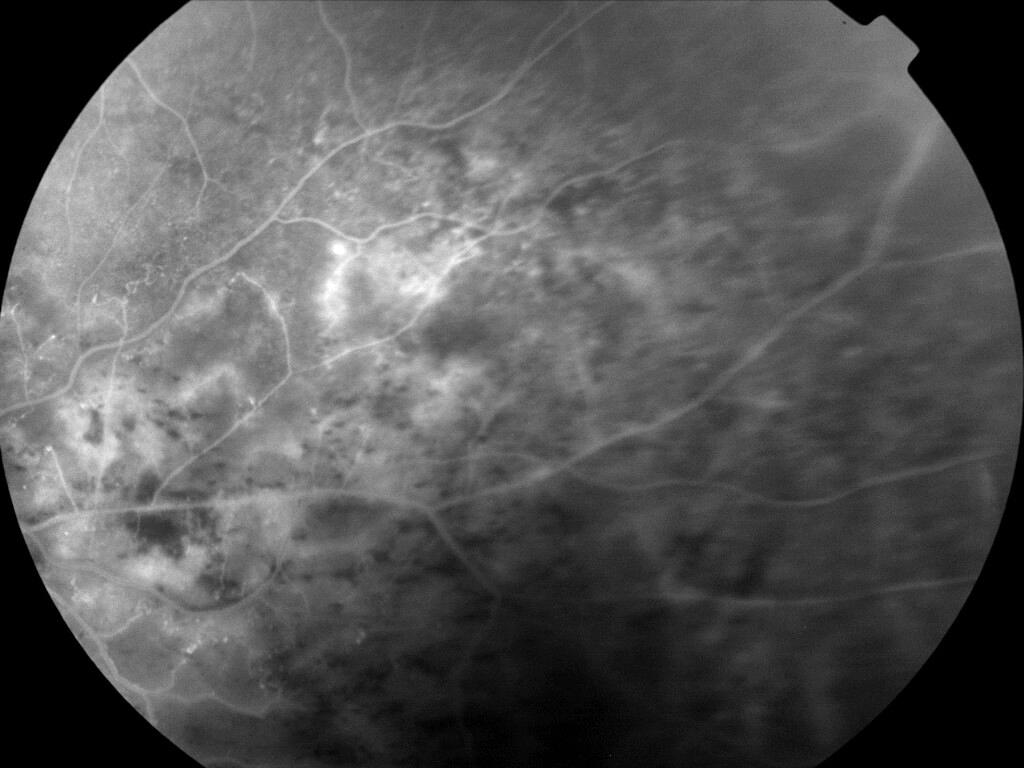

OCCLUSION DE BRANCHE DE LA VTS DE FORME ISCHEMIQUE MAJEURE